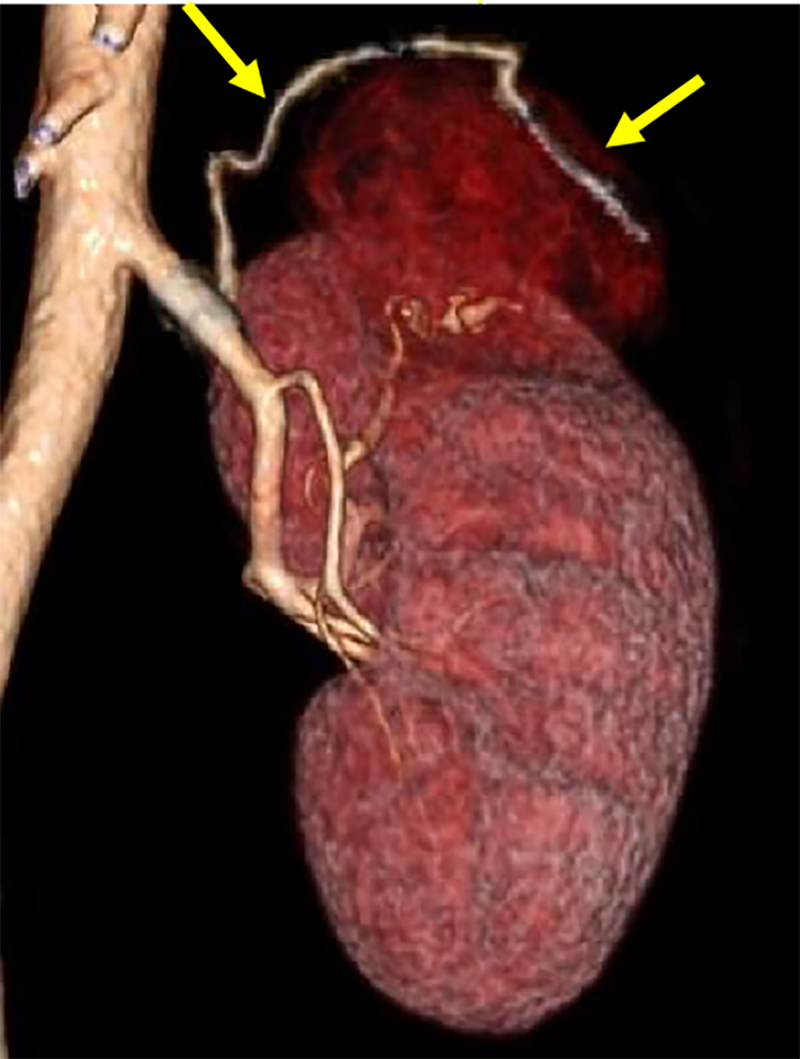

本症例では術前の造影CTから左腎動脈上極枝のほか、左腎動脈本幹から分岐する左上腎被膜動脈が栄養血管として同定され、この画像情報を参考にして塞栓術が施行された。術中の血管造影においても左上腎被膜動脈が腫瘍を栄養する血管として確認され、術前の造影CT所見の通りであった。

この早期動脈相は術前の腎動脈解剖を詳細に把握するために最も重要な撮影時相である。薄層スライス厚での撮影により、高精細なMPR(多断面再構成)、MIP(最大値投影法)による3D画像処理が可能となり、腎動脈の起始部から末梢分枝まで、さらに異所性分岐などの解剖学的バリエーションも明瞭に描出できる。特に塞栓術においては、標的血管の同定と周囲血管との関係性の把握が重要であり、これらの三次元的な血管構築の評価は手技の成功に直結する。このようにbolus tracking法を用いた精密なタイミング制御と高分解能撮影の組み合わせにより、塞栓術の安全かつ確実な施行に必要な血管解剖情報を包括的に取得している。